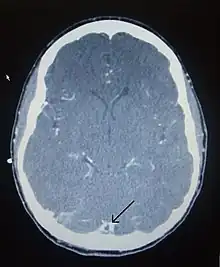

Computed tomography, with radiocontrast in the venous phase (CT venography or CTV), has a detection rate that in some regards exceeds that of MRI. The test involves injection into a vein (usually in the arm) of a radioopaque substance, and time is allowed for the bloodstream to carry it to the cerebral veins – at which point the scan is performed. It has a sensitivity of 75–100% (it detects 75–100% of all clots present), and a specificity of 81–100% (it would be incorrectly positive in 0–19%). In the first two weeks, the "empty delta sign" may be observed (in later stages, this sign may disappear).[11] The empty delta sign is characterized by enhancement of the dural wall without intra-sinus enhancement.[6]